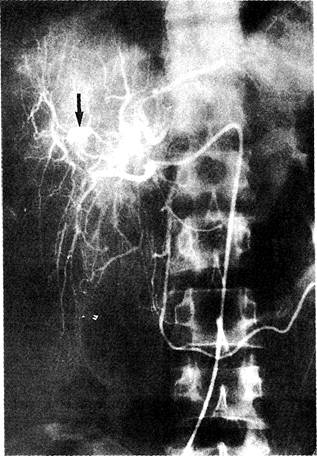

Аневризма печёночной артерии у больного с подострым бактериальным эндокардитом на ангиографии